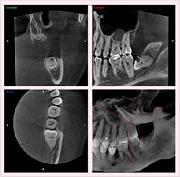

CT画像からは、骨の形や欠損状態がわかるだけでなく、神経の位置や向きなどもしっかり把握できますので、特に、以下のような治療で役立っています。

◆インプラント

◆親知らず